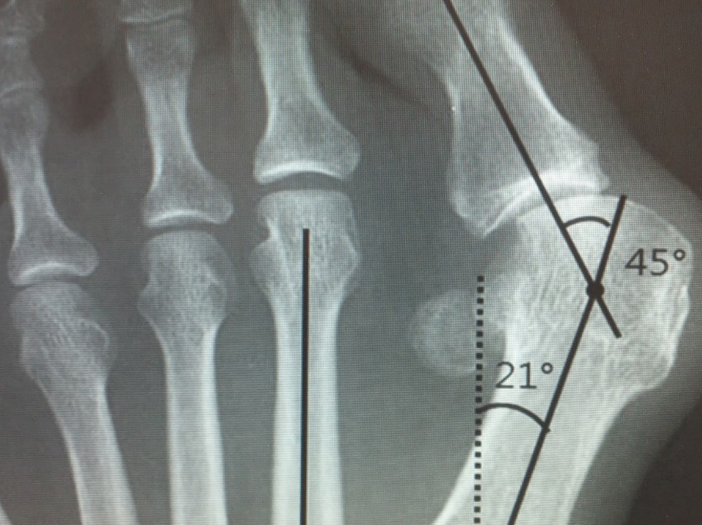

우리가 흔히 알고 있는 무지외반증 때문입니다. 사전적 의미는 엄지발가락이 안쪽으로 튀어나오는 변형이 생겼다는 말입니다. 하지만 실제로 따지고 보면 발가락과 발등을 연결하는 중족골이라는 뼈가 안쪽으로 벌어지면서 회전 변형이 같이 일어나는 질환입니다. 처음에는 증상이 없다가도 점차 진행하게 되면 발가락 안쪽이 점차 튀어나와 일반적인 신발을 신기가 불편한 증상이 생깁니다.

보행 시 첫번째 중족골이 힘을 잘 받쳐줘야 하는데 무지외반이 진행되면 다른 발가락의 중족골이 힘을 받으며 발바닥 쪽의 통증이 생기는 전이성 중족골통이 발생하기도합니다. 또한 심한 변형이 지속되면 발가락을 움직여주는 힘줄이 제 역할을 하지 못해 걷기 불편하기도 하며, 엄지발가락이 두번째 발가락을 밀면서 두번째 발가락까지 점차 변형이 진행되고 엄지발가락이 검지발가락에 올라타는 변형이 발생하기도합니다.

수술적 치료 방법은 증상과 정도에 따라 여러 가지 방법을 선택할 수 있습니다. 가장 대표적인 수술은 문제가 되는 엄지발가락 쪽의 제1중족골을 절골, 즉 부러뜨려서 이동시킨 뒤에 금속 나사 등으로 고정하는 방법입니다. 전통적으로 안쪽 피부 절개를 하여 수술을 시행했으나 최근에는 절개를 최소화 한 최소침습 무지외반 교정술 방법이 알려져 있어 환자들의 수술 후 회복이 매우 빨라졌습니다. 무지외반증으로 고생하고 있는 분들이 있다면 정확한 진단과 치료 방법에 대하여 정형외과 전문의와 상의하길 권장합니다